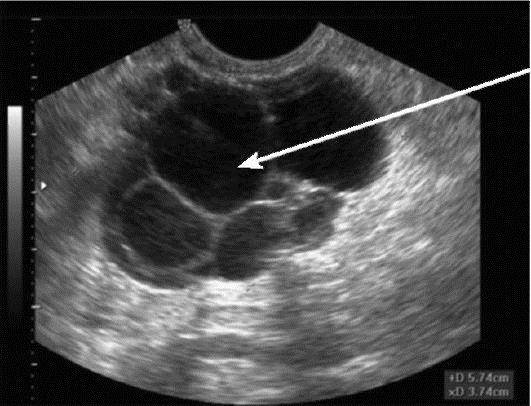

В процессе УЗИ специалист определяет расположение новообразований, а также их характеристику, формы и непосредственные размеры. Чтобы отличить доброкачественную кистому от злокачественной, врачом может проводиться специальное цветовое доплеровсое картирование. С его помощью подтверждается наличие или отсутствие кровотока в новообразовании, чем и отличается характер опухоли.

Воспаление придатков на УЗИ

Воспаление маточных труб сопровождается экссудацией жидкости в просвет — гидросальпинкс. На УЗИ между маткой и нормальным яичником определяется вытянутой формы одно- или многокамерное анэхогенное образование с тонкими стенками. При хроническом сальпингите стенка маточных труб утолщена, по периферии гиперэхогенные мелкие (2-3 мм) структуры по типу «бисера»; в просвете неоднородная взвесь.

Рисунок. Женщина с жалобами на тянущие боли внизу живота, появились нескольких дней. Матка и правый яичник удалены 4 года назад. На УЗИ левый яичник соприкасается с анэхогенной трубчатой структурой с неполными перегородками. Заключение: Гидросальпинкс слева.

Рисунок. На УЗИ между маткой и яичником определяется многокамерная анэхогенная структура, стенки толстые с мелкими гиперэхогенными включениями по типу «бисера», в просвете мелкодисперсная взвесь и уровни. Заключение: Хронический сальпингит.

Кистомы яичника

– серозные и муциноз-ные эпителиальные доброкачественные опухоли. Морфологически различают гладкостенные и папиллярные кистомы. Гладкостенная серозная кистома представляет собой шаровидное одно- или многокамерное образование с тонкими стенками, содержащее светлую опалесцирующую жидкость, выстланное изнутри мерцательным эпителием. Как правило, опухоль односторонняя, небольшая, но встречаются опухоли, масса которых достигает нескольких килограммов. Папиллярная серозная кистома отличается от гладкостенной наличием сосочковых разрастаний на внутренней поверхности, а иногда и снаружи. Нередко поражаются оба яичника, возникают сращения с соседними органами, асцит. Серозные кистомы развиваются чаще в пре-и постменопаузе. Муцинозные кистомы получили свое название из-за слизеподобного содержимого. Опухоли, как правило, многокамерные, имеют дольчатую поверхность за счет выбухающих отдельных камер, могут достигать больших размеров. При папиллярных муцинозных кистомах с разрастанием сосочков на поверхности опухоли нередко возникает асцит. Муцинозные кистомы наблюдаются обычно в возрасте 40-60 лет, папиллярные опухоли – в постменопаузе.